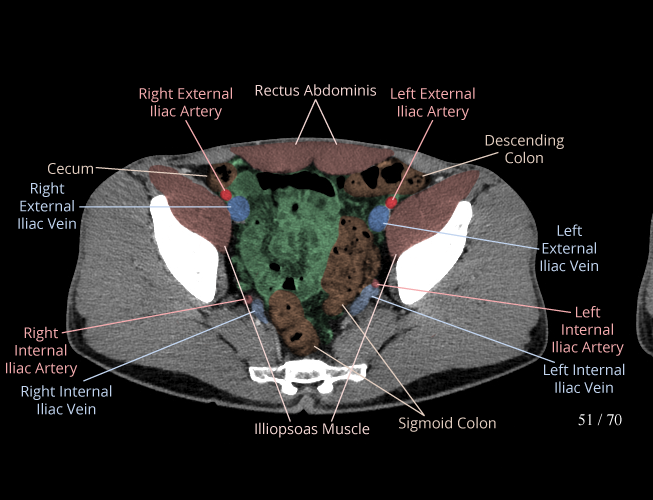

Pelvis

Covers pelvic MRI anatomy.